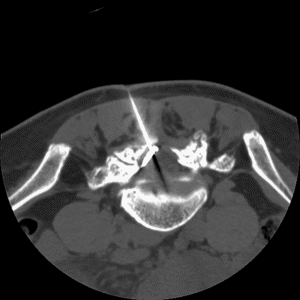

Les radiologues interventionnels utilisent des techniques d’imagerie (échographie, scanner, angiographie) pour réaliser des procédures mini-invasives à visée thérapeutique qui viennent en complément ou en alternative à la chirurgie.

Ces techniques permettent de traiter diverses pathologies sans nécessiter de grandes incisions, les patients n’ont donc pas de cicatrice au décours de l’intervention. Les procédures de radiologie interventionnelle sont souvent moins risquées et plus rapide que la chirurgie traditionnelle.